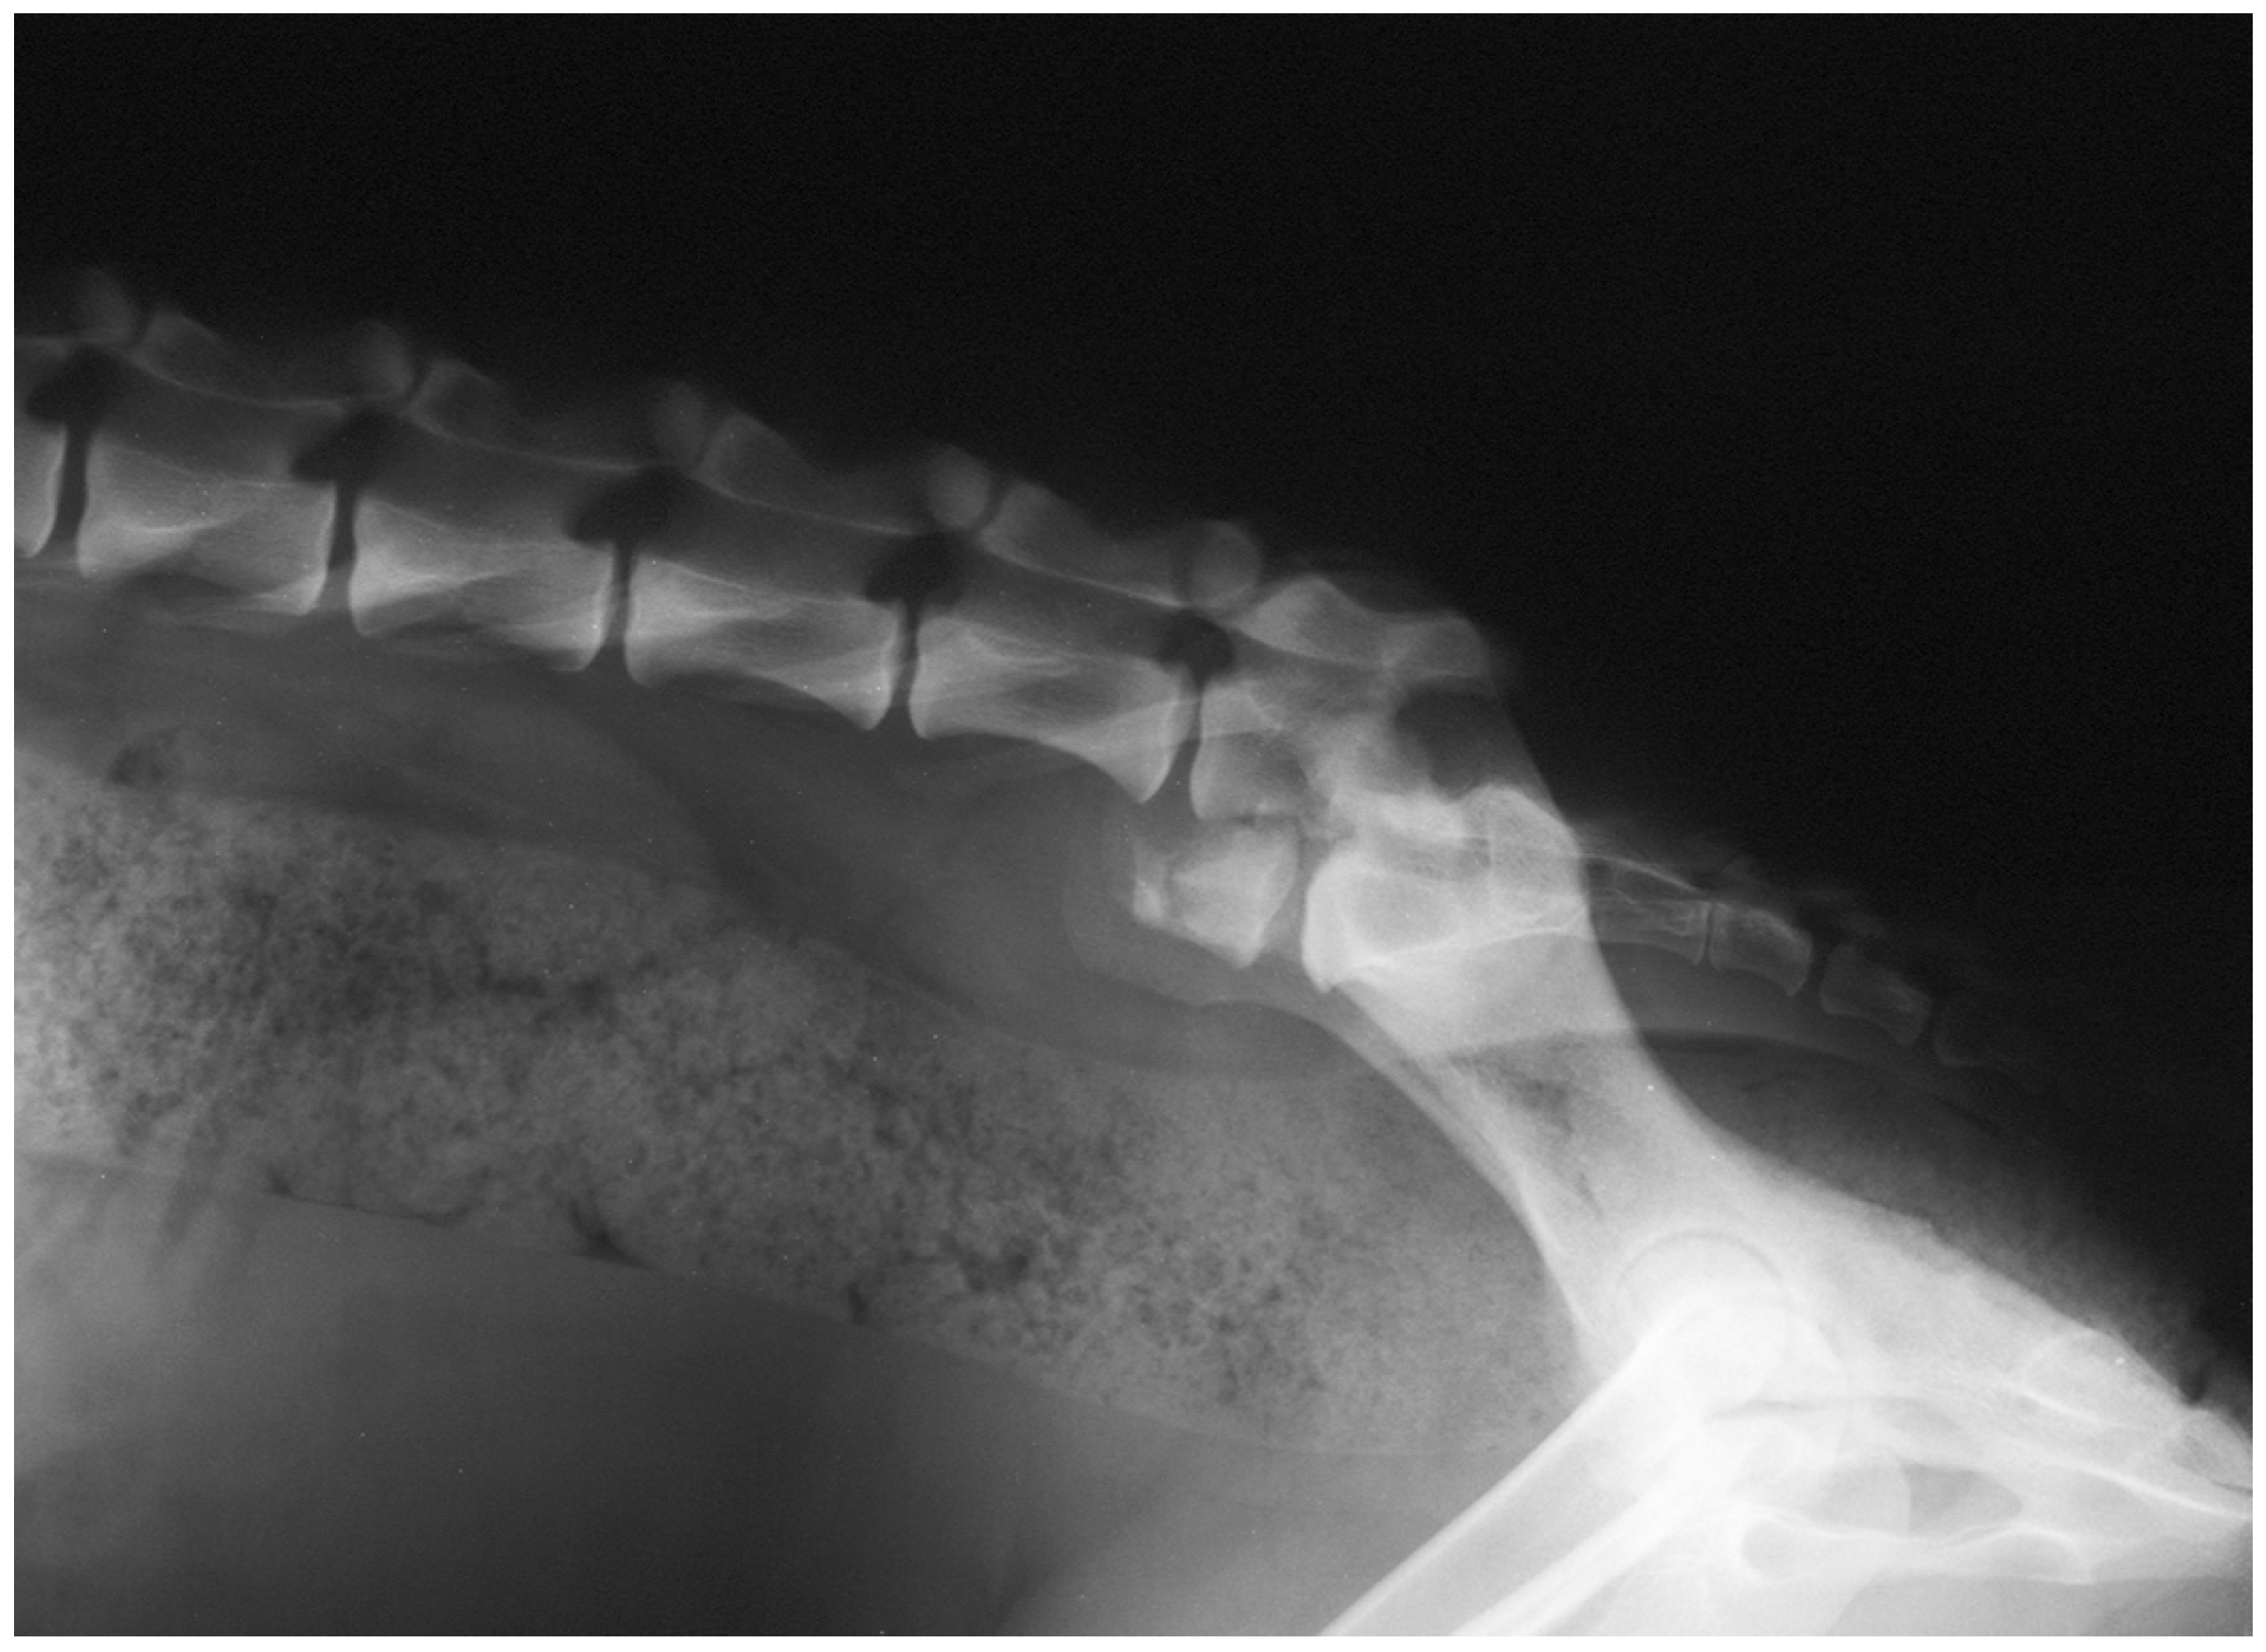

3.4. Imaging